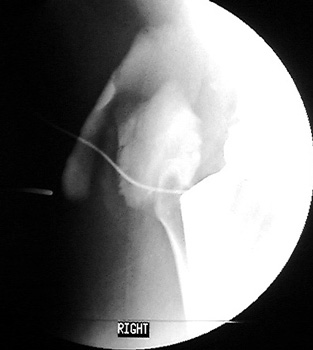

Normal arthrogram

Dry tap

DDx:

- Dry joint

- Large periarticular bursa acting as sump for fluid

- Sinus track allowing for continuous drainage of joint

- Non bacteriostatic saline wash performed